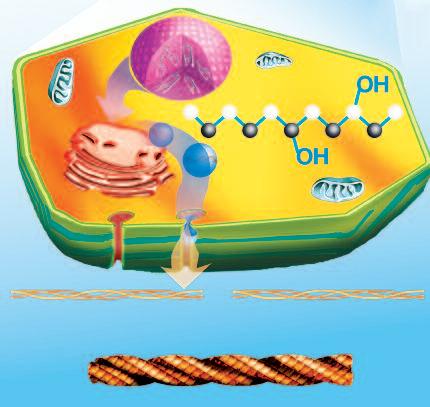

La produzione ottimale di molecole di collagene è fondamentale per un sano tessuto connettivo e costituisce la base per un efficace controllo del cancro e di altre malattie. L’immagine nella pagina a fronte illustra le fasi importanti della produzione di collagene all'interno di una cellula e descrive il ruolo essenziale di alcuni micronutrienti in questo processo.

La produzione ottimale e la struttura del collagene dipende in modo critico da tre micronutrienti:

• Vitamina C controlla la produzione di collagene a livello del nucleo cellulare. Inoltre, i filamenti di collagene appena sintetizzati, si annodano uno intorno all'altro come una corda intrecciata, hanno bisogno di questa vitamina per raggiungere la stabilità ottimale. A tal fine, la vitamina C catalizza la formazione di ‘ponti’ chimici tra le fibre di collagene separate, che stabilizzano l'intera struttura

• La lisin a è un elemento importante della catena di aminoacidi e costituisce la molecola più importante del collagene. Poiché il nostro corpo non può produrre lisina, ogni singola molecola di lisina deve essere fornita dalla dieta o attraverso integratori alimentari.

• La p rolin a è un aminoacido componente importante del collagene. A differenza della lisina, la prolina può essere prodotta dal nostro corpo, ma solo in quantità limitate. Se una persona soffre di una malattia cronica, associata ad una degradazione enzimatica a lungo termine del collagene, la capacità dell’organismo di produrre prolina può essere esaurita o insufficiente. Questo porta spesso ad una relativa carenza di prolina con conseguenze note quali debolezza del tessuto connettivo, che a sua volta, facilita la progressione della malattia.

Gli aminoacidi prolina e lisina sono unità fondamentali per la produzione di tessuto connettivo

Vitamina C

Controlla la produzione di collagene nel nucleo

Prolina

Unità fondamentale del collagene, spesso non prodotta a sufficienza dal corpo

Lisina

Unità fondamentale del collagene, assunta esclusivamente tramite l’alimentazione

Kollagenmolekül

Vitamina C

Forma un gruppo idrossilico OH necessario per consolidare le fibre di collagene, fortificando il collagene medesimo